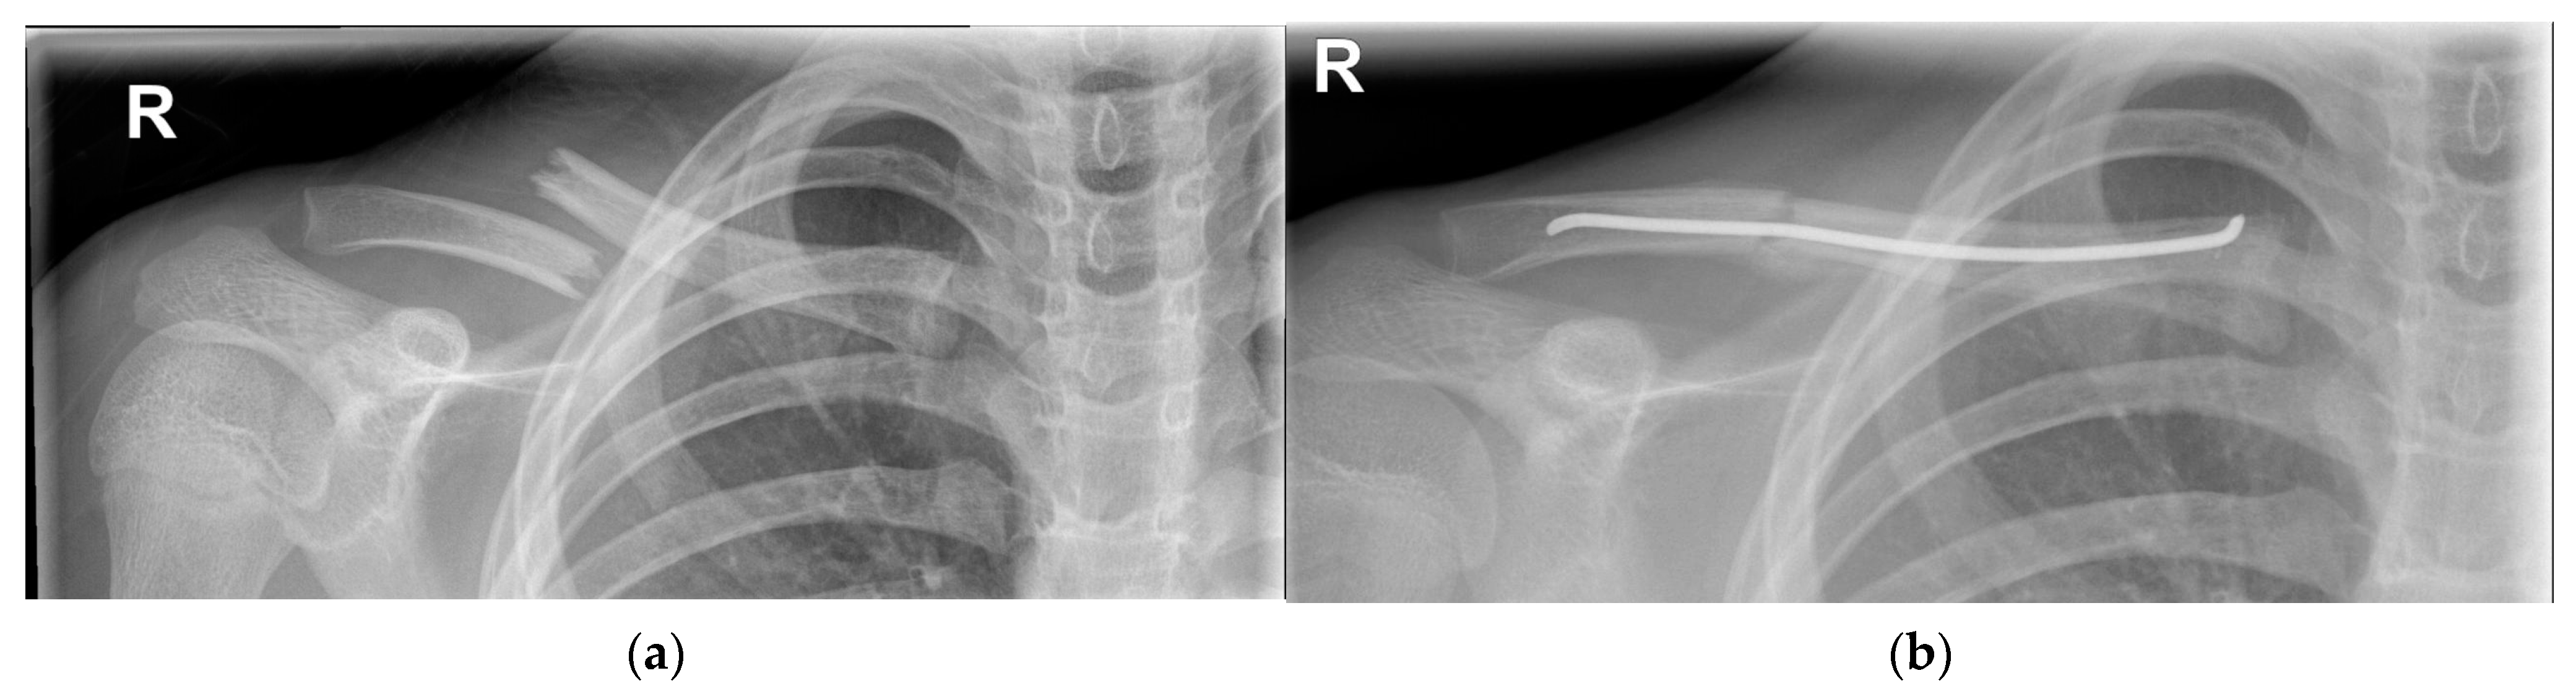

4.1.2. Operative Treatment